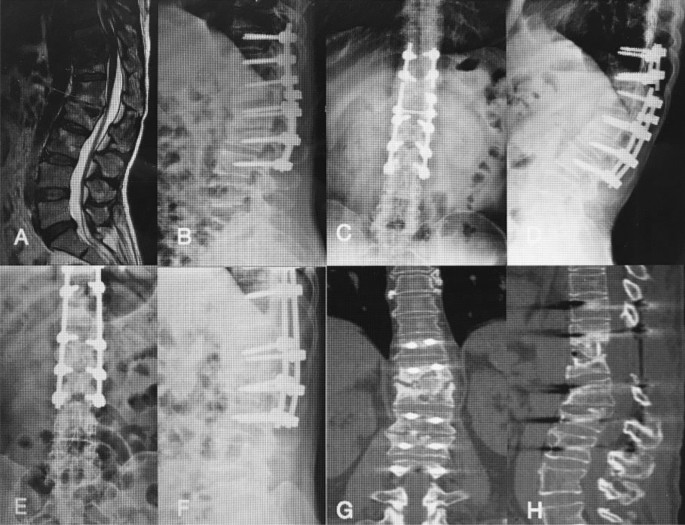

The thoracic spinal TB was well cured and all patients achieved bony fusion at a mean 12.90 ± 3.91 months. The mean angle of 24.35 ± 5.74° preoperatively showed a significant difference between 1 week postoperatively and final FU. Although there were the loss of angle at final FU comparing with the 1 week postoperatively, it still maintain the good alignment and the segmental stability (Figs. 3, 4). One case of rod fracture was observed 2 years postoperatively, and the revision surgery was performed with an iliac graft (Fig. 5). Some postoperative complications occurred, such as water-electrolyte imbalance (two cases) and superficial infection (two cases).

A 28-year-old female patient with lumbosacral spinal tuberculosis (L5-S1) underwent posterior debridement and decompression combined with instrumentation. (A,B) Preoperative computed tomography (CT) shows bone destruction of the L5-S1 vertebrae and compression of the nerve, and 1-week X-ray shows the correction was maintained. (C–E) The 6-month postoperative X-ray and 6-month postoperative CT show the correction was maintained, but the bone was not fully healed. (F) The 1-year and 2-year postoperative X-rays show the kyphosis correction has been maintained. (G–I) At 4-year follow-up, plain X-ray and CT show solid bone fusion.